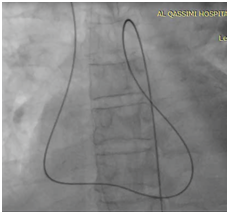

Patient deteriorated rapidly so intra-aortic balloon pump IABP and high doses of inotrops were started. We planned to closed this VSD by device in the catheterization laboratory on the same time but unfurtunalilly was did not have the suitable VSD dives size and No post MI device at all. Patient was shifted to cardiac intensive care unit for close observation and continue on inotrops, IABP and ventilation waiting for the suitable device. He remined stable slightly and after 5 days we prepared for post MI device closure since we obtained post MI VSD devices. The procedure was done under general anesthesia since the patients sedated and Trans jugular venous approach and femoral artery we created Arterio-venous loop (Figure 2) and throw 12 F sheath a 20 mm post MI VSD device closure was deployed successfully in place according to VSD device closure techniq under the guidance of trans-esophageal echocardiography and fluoroscopy (Figure 3).